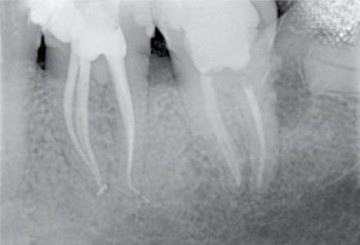

Preoperative x-ray: Upon diagnosis of pulp necrosis an initial endodontic treatment is indicated. The mesial root canals present a mineralized root canal lumen and a strong curvature and the distal canal an extremely curved apical third.